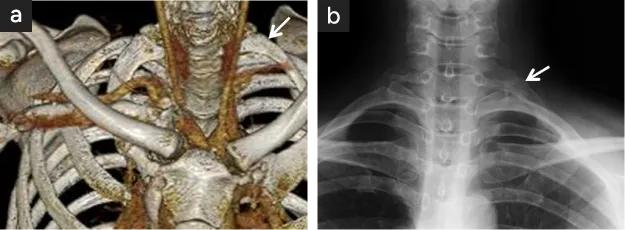

図11

図11. 適切な第一肋骨切除法

• 【切除された左第一肋骨】図の追加部分まで切除され上端は椎体横突起との関節(矢印)

• 術後のX線撮影で、関節(矢印)まで切除されていることが確認される。